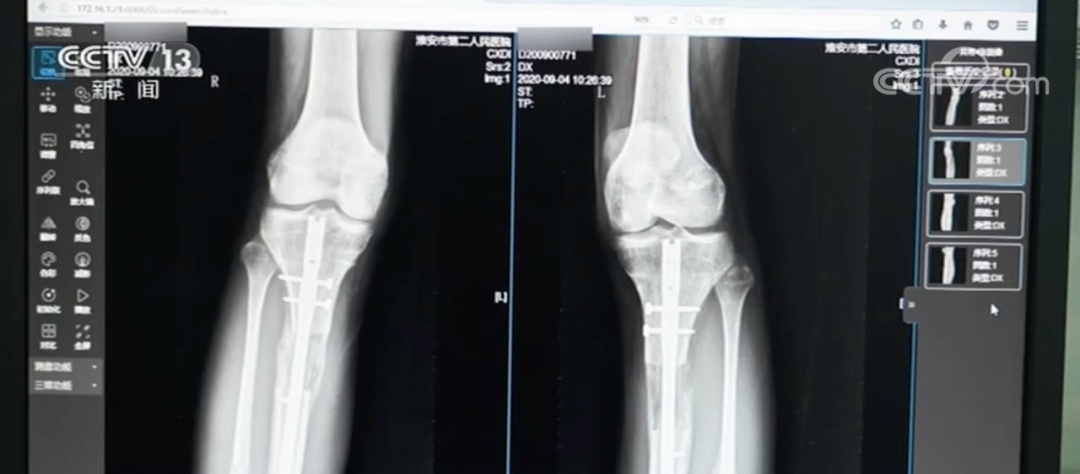

术中截断腿骨术后

小梦告诉记者,外架手术需要截断腿骨,用钢针穿透皮肤肌肉固定断骨,外部用圆环加固。术后每天需要调整支架旋钮拉伸双腿,全程需要一年半时间。内置手术则是沿腿骨植入电磁驱动髓内延长钉,通过体外遥控牵引,术后仅留2厘米微小疤痕且恢复期只有3个月时间。

术后第六个月,并发症突然来袭。小梦右小腿断骨处出现红肿溃烂,脓液不断渗出,被确诊为急性骨髓炎。当时她住在医疗机构安排的酒店里,“每天护士只负责帮我涂碘伏和换纱布。

虽然小梦后续在国内接受了X型腿矫正手术,但效果并不理想。

江西南昌一名19岁的女生原本身高1米54,做了胫腓骨延长手术后,虽然增高了6厘米,但出现行走障碍。经检查,她的膝关节与踝关节都已经僵硬,不能完全靠自己站起来,需要依靠拐杖辅助行走。